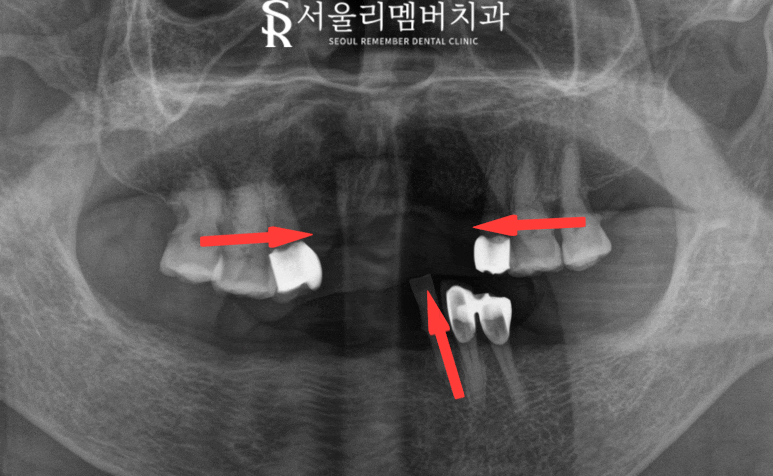

사진을 보면

한눈에 봐도 비어 보이는 치아들을 볼 수 있는데요.

x-ray를 보면서 더 자세하게 검진하겠습니다.

방향으로 표시한 곳을 보면

1️⃣ 빈 곳으로 치아 이동

2️⃣ 대합치 정출

3️⃣ 치조골 퇴축

다른 문제도 많지만 크게 이렇게 3가지가 있습니다.

그리고 위에서 찍은 사진을 봐도

치조골 두께 자체도 얇아진 것을 관찰되었는데요.